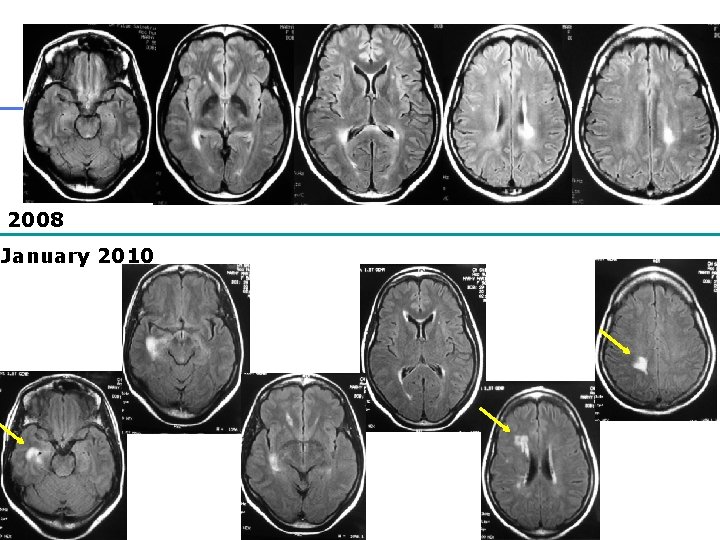

IRM encéphalique Pittock et al, 2006 Arch Neurol • N=60 patients • Durée de suivie: 6 ans +/- 5 • 36 anomalies cérébrales (60%)

2008 January 2010 32

• Après 3 ans d’évolution: – Ac anti-NMO + – Myélite cervicale

Nouveaux critères Wingerchuk et al, 2006, Neurology • Névrite optique • Myélite aigue • 2 critères sur 3: 1. IRM médullaire: 1 HS T 2 étendu ≥ 3 corps vertébraux 2. IRM cérébrale ne remplissant pas les critères de SEP 3. Ig. G anti-aquaporine 4 sensibilité 99%, spécificité 90%